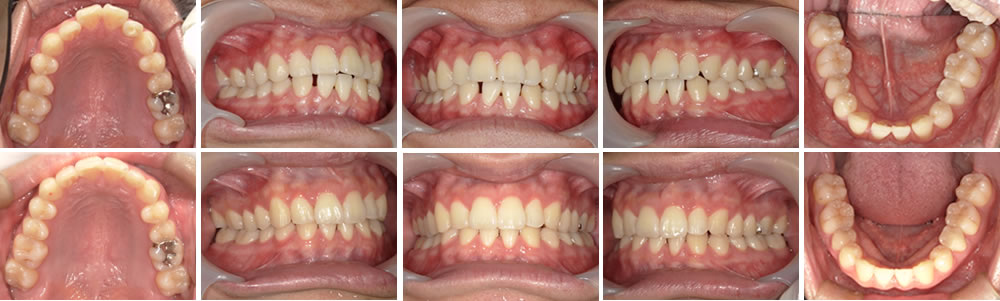

マウスピース矯正(インビザライン)で八重歯を改善した症例

年齢

30代

性別

女性

マウスピース矯正(インビザライン)で前歯のがたつきを改善した症例

20代

男性